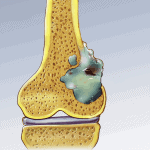

U nguyên bào sụn (Chondroblastoma) là tổn thương hiếm gặp và thường xảy ra ở sụn trong giai đoạn đang hoàn tất quá trình phát triển. Có đến 90% các ca bệnh u nguyên bào sụn gặp ở những người 5 – 25 tuổi, nam giới có nguy cơ mắc phải bệnh này cao gấp đôi so với nữ giới. U nguyên bào sụn hay gặp ở vùng sụn phát triển ở đầu trên xương cánh tay và xung quanh gối, triệu chứng chủ yếu là đau lan vào khớp, có thể gây sưng nề tại chỗ và hạn chế vận động của những khớp liên quan…